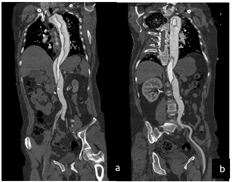

如下轴位图所见:头臂干、左颈总动脉、左锁骨下动脉管腔亦呈双腔样改变(图2a~b)。右肾动脉起自真腔,左肾动脉起自假腔,显影差(图2c~d)。

Ⅰ型主动脉夹层,夹层范围上自主动脉根部下至右侧髂内外动脉、左侧髂总动脉起始部,夹层累及右冠状动脉、头臂干、左颈总动脉、左锁骨下动脉、腹腔干及左肾动脉;右侧髂总动脉及髂内外动脉大范围受累显影差并血栓形成;左肾显影差。